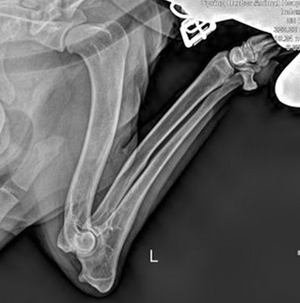

Natasha lt elbow 300 Natasha rt. elbow 300w

Natasha OFA Elbows Normal